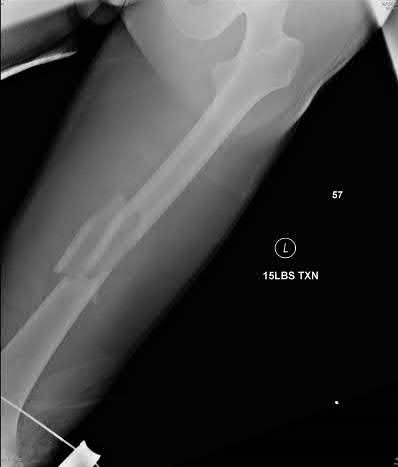

A 32-year-old male sustains a closed tibia fracture and develops intense leg pain out of proportion to the injury. You suspect acute compartment syndrome.

Which of the following pressure parameters is considered the most reliable threshold indication for performing a four-compartment fasciotomy?

Explanation

The differential pressure (Delta P) is universally recognized as more reliable than absolute compartment pressure for diagnosing acute compartment syndrome. A Delta P is calculated by subtracting the intracompartmental pressure from the patient's diastolic blood pressure. A Delta P of less than 30 mmHg represents inadequate tissue perfusion pressure and is an absolute indication for emergency fasciotomy.